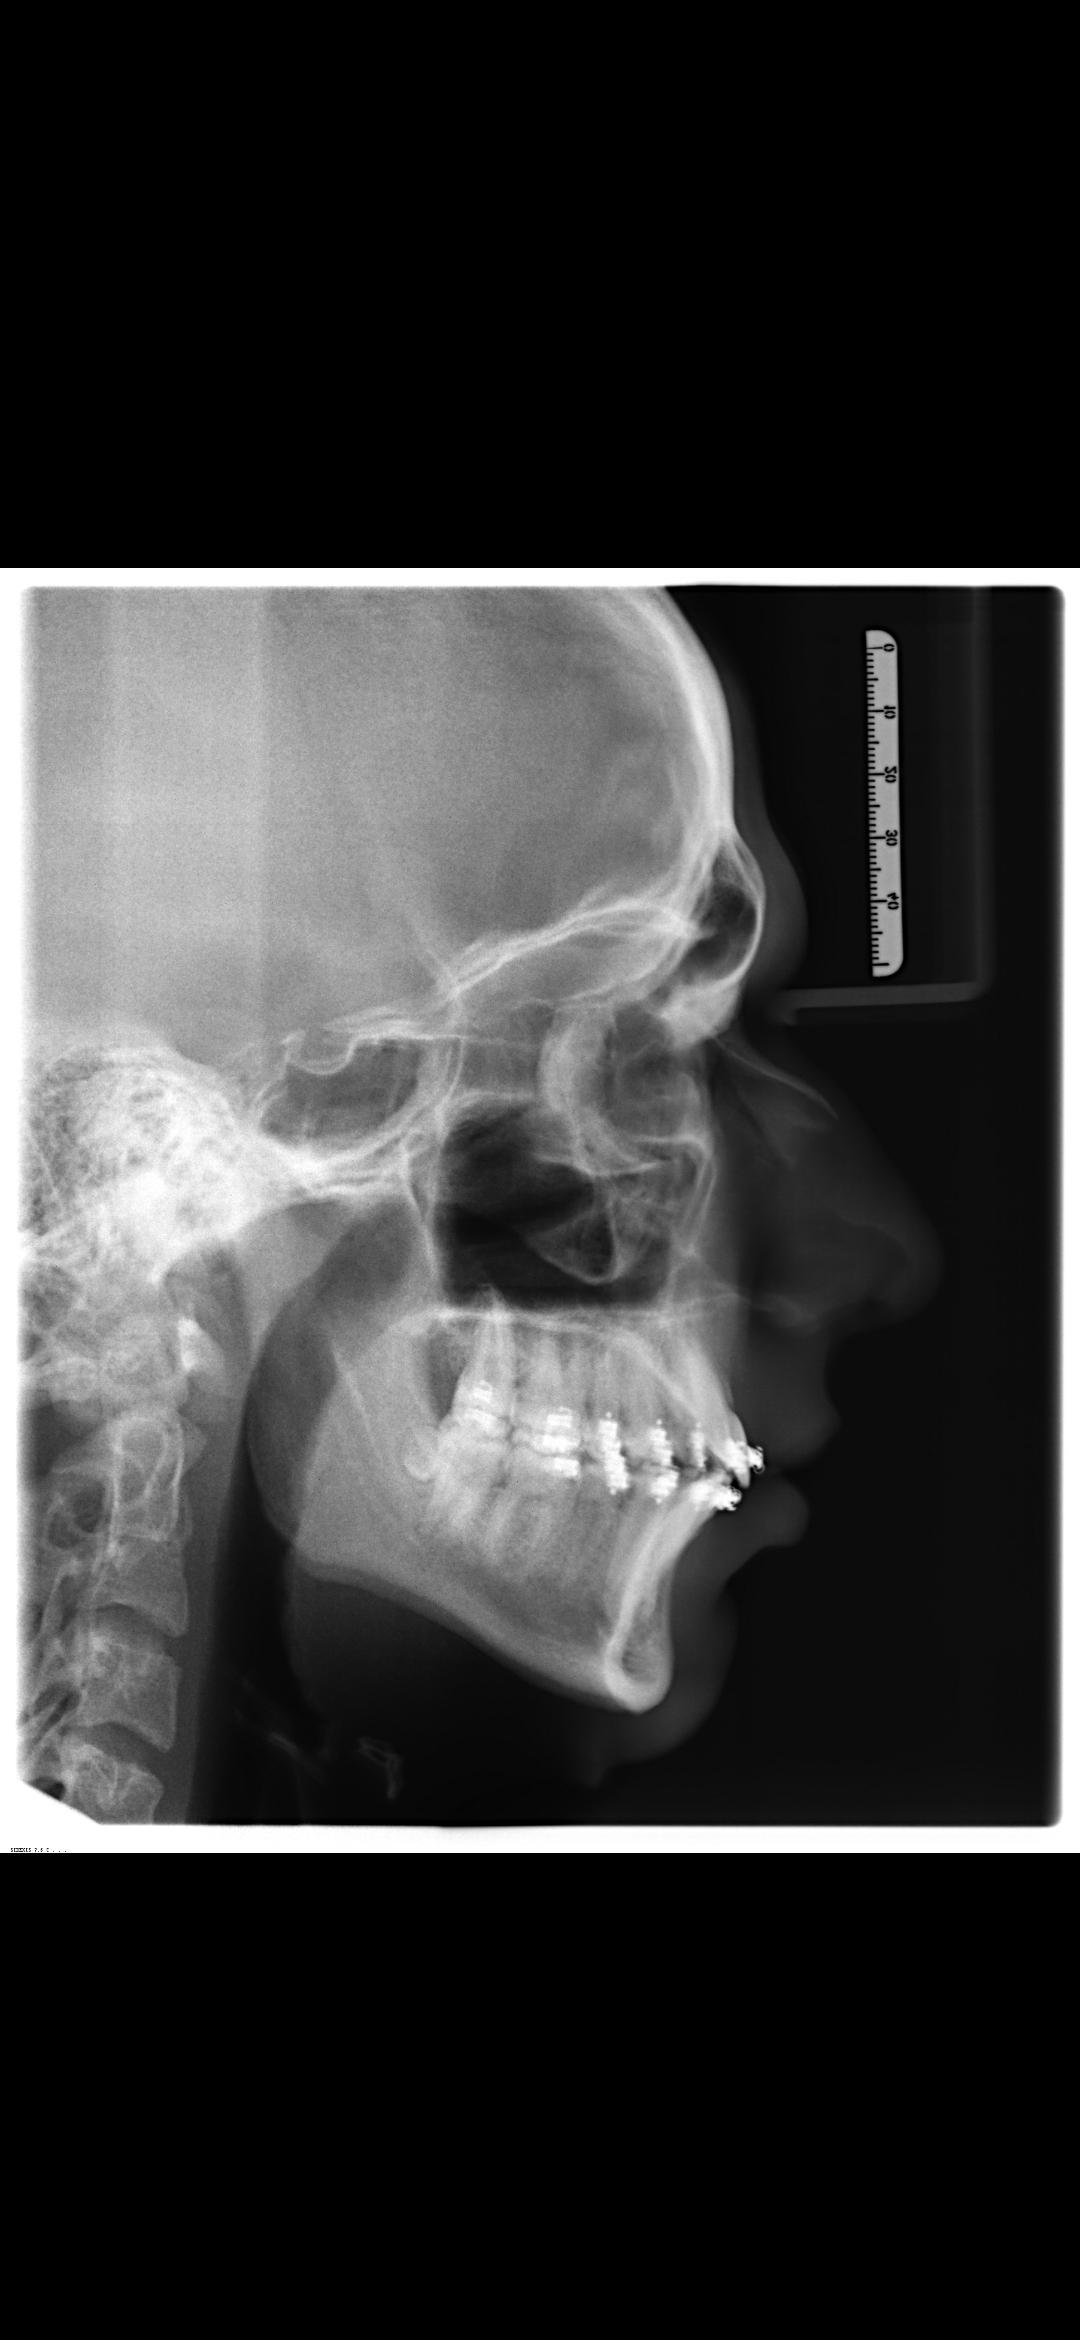

I'm getting Bimax in 5 weeks, and it's getting planned next week, but i don't know how much mm of forward movement i should get. My bite is perfect but my chin is recessed (which will be fixed by a Genioplasty), aside from that my mandible and maxilla are retrognathic (too short), which will be fixed through dysgnathia (the forwardmovement of both jaws). I think around 12mm of forward movement in maxilla and mandible + genioplasty would be perfect, i'm not sure tho, what do yall think, if you have experience with jaw surgery?